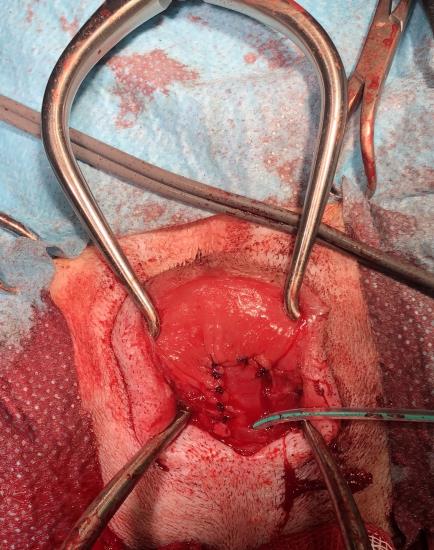

Delilah was then anaesthetised and taken to surgery. The urethra was identified and catheterised (Fig 3) and an episiotomy performed to give safe access to the urethral orifice. The pseudophallus was then gradually dissected free from its attachments (Fig 4) and a mucosal flap containing the urethral orifice was raised and separated from the phallus using a harmonic scalpel (Fig 5). The phallus was then amputated and the mucosal flap and urethra were then sutured into the mucosal defect left from phallus removal (Fig 6).